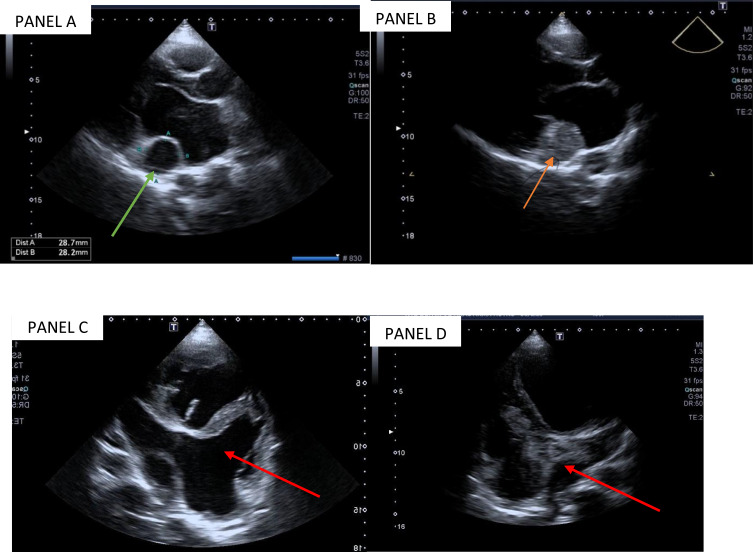

Case presentation: We report the case of a 45-year-old male who presented with progressive symptoms of heart failure, including dyspnea, fatigue, and reduced exercise tolerance. Initial workup revealed an unexplained dilated coronary sinus and reduced left ventricular function with dilated heart chambers. Further imaging with contrast-enhanced echocardiography and CT angiography confirmed the presence of a PLSVC draining into the coronary sinus with absence of right superior vena cava. No other congenital heart defects were identified like coronary sinus atrial septal defect (ASD). The delayed diagnosis of PLSVC likely contributed to chronic atrial stretch, arrhythmia development- atrial fibrillation in this case, and eventual heart failure symptoms.